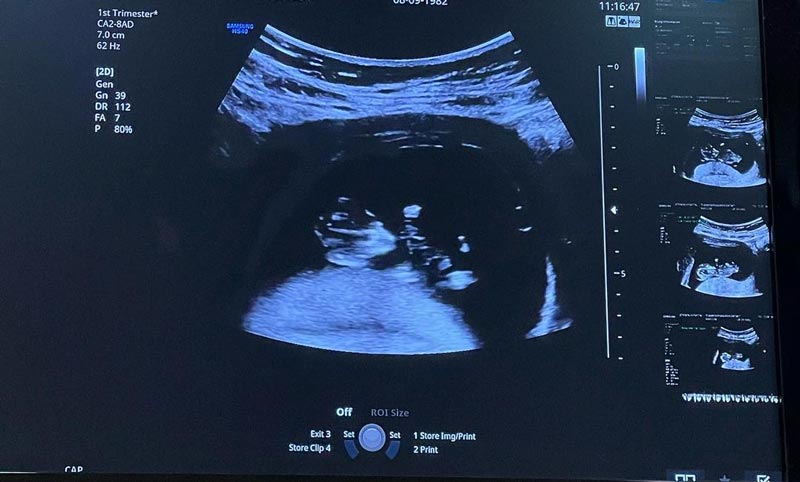

ล่าสุด (16 มกราคม 2565) สาวแยม ก็ได้ออกมาเปิดเผยข่าวดีต้อนรับปีใหม่ หลังตั้งครรภ์ทายาทคนที่ 3 เป็นที่เรียบร้อยแล้ว พร้อมเผยภาพอัลตราซาวด์ลูกน้อยในท้องที่ตอนนี้มีอายุครรภ์ได้ 13 สัปดาห์แล้ว และแคปชั่นลงอินตาแกรมส่วนตัวว่า "Hi!!! No.3 #13weekspregnant"